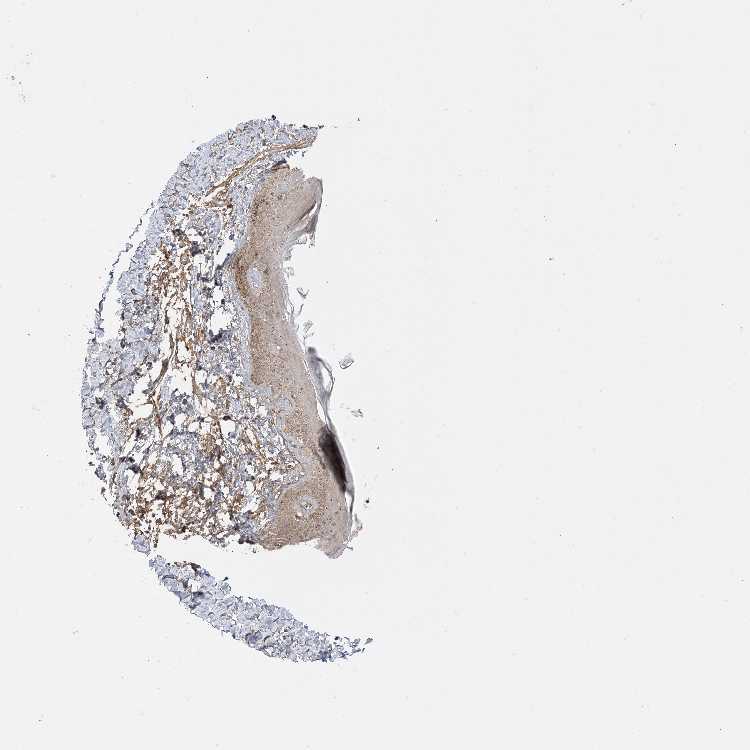

SKIN 1 - Antibody stainingi

Antibody staining in the annotated cell types in the current human tissue is reported as not detected, low, medium, or high, based on conventional immunohistochemistry profiling in selected tissues. This score is based on the combination of the staining intensity and fraction of stained cells.

Each image is clickable and will lead to virtual microscopy that enables deeper exploration of all samples and also displays staining intensity scores, fraction scores and subcellular localization as well as patient and tissue information for each sample.

Antibody CAB037142

Langerhans Medium

Fibroblasts Medium

Keratinocytes Medium

Melanocytes High

SKIN 2 - Antibody stainingi

Epidermal cells High